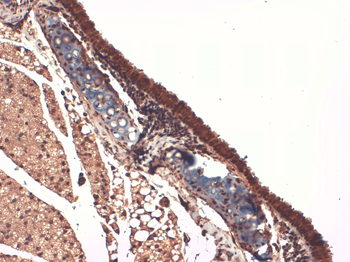

Immunohistochemical staining of paraffin embedded mouse ovary tissue using NIS antibody (2.5 ug/ml)